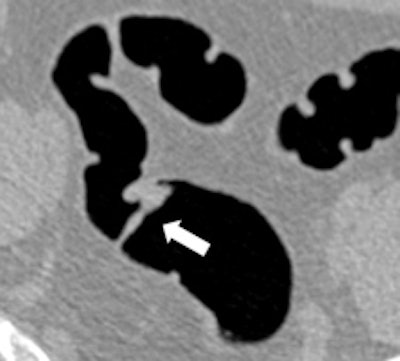

Left: Large pedunculated polyp in the sigmoid (white arrow). Right: Corresponding 3D image of this pedunculated polyp with a 2-cm head (white arrow). Images courtesy of Philippe Lefere, MD.Moreover, the procedure is patient-friendly and it can be performed on an outpatient basis. No sedation is necessary, the examination time is short, it can be performed the same day as the optical colonoscopy, it can detect important pathology outside of the colon, and patient preparation is possible without interruption of normal daily activities, Lefere said. The main drawbacks are that radiation is used, polypectomy is not possible, there is the potential for superfluous explorations (iatrogenic pathology), patient preparation is still needed, it involves a relatively steep learning curve, and long interpretation times during the initial phase.